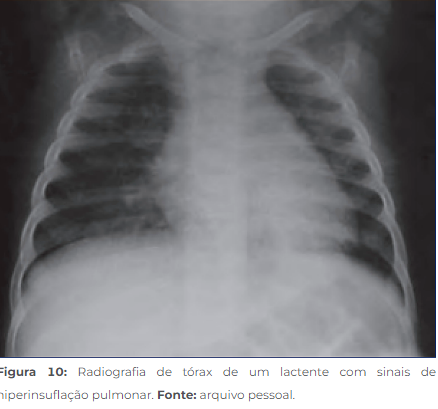

• Raio-X(acima): hiperinsuflação pulmonar (retificação de arcos costais e diafragma, maior número de espaços intervertebrais visualizados)